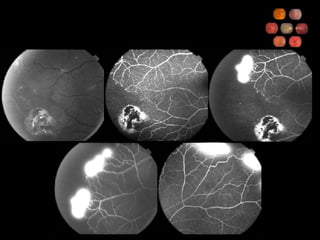

62 yo diabetic 20/60

Diabetic Retinopathy WESDR IDDM  99% have retinopathy after 20 yr NIDDM 60% have retinopathy after 20 yr DCCT Tight glucose control decreases retinopathy in IDDM UKPDS Glucose control decreases retinopathy in NIDDM

Diabetic Retinopathy ETDRS Focal laser indicated for CSME Retinal thickening at or within 500   m of the foveal center Retinal thickening associated with hard exudate at or within 500   m of the foveal center A zone of retinal thickening larger than 1 disc area within 1 disc diameter of the foveal center PRP indicated for high risk PDR, not for NPDR (can consider for severe NPDR) ASA does not affect vitreous hemorrhage

Diabetic Retinopathy Describe the 4:2:1 rule 4 quadrants of diffuse intraretinal hemorrhage and microaneurysms 2 quadrants of venous beading 1 quadrant of intraretinal microvascular abnormalities What is severe NPDR and what 1-year risk does it carry for progression to high-risk PDR? 1 of the above criteria 15% What is very severe NPDR and what 1-year risk does it carry for progression to high-risk PDR? 2 of the above criteria 45%

Diabetic Retinopathy DRS - PRP reduces severe visual loss by 50% for high risk PDR Mild (1/4 to 1/3 disc area) NVD with vitreous hemorrhage Moderate to severe NVD with or w/o vitreous hemorrhage Moderate (1/2 disc area) NVE with vitreous hemorrhage DRVS - vitrectomy for nonclearing vitreous hemorrhage Early vitrectomy beneficial for IDDM Early (1 mo) same as late (6 mo) for NIDDM Other indications for surgery Macula involving TRD Combined TRD/RRD Refractory macular edema with taut posterior hyaloid

Diabetic Retinopathy WESDRIDDM 99% have retinopathy after 20 yr NIDDM 60% have retinopathy after 20 yr DCCT Tight glucose control decreases retinopathy in IDDM UKPDS Glucose control decreases retinopathy in NIDDM

Diabetic Retinopathy ETDRSFocal laser indicated for CSME Retinal thickening at or within 500  m of the foveal center Retinal thickening associated with hard exudate at or within 500  m of the foveal center A zone of retinal thickening larger than 1 disc area within 1 disc diameter of the foveal center PRP indicated for high risk PDR, not for NPDR (can consider for severe NPDR) ASA does not affect vitreous hemorrhage

Diabetic Retinopathy Describethe 4:2:1 rule 4 quadrants of diffuse intraretinal hemorrhage and microaneurysms 2 quadrants of venous beading 1 quadrant of intraretinal microvascular abnormalities What is severe NPDR and what 1-year risk does it carry for progression to high-risk PDR? 1 of the above criteria 15% What is very severe NPDR and what 1-year risk does it carry for progression to high-risk PDR? 2 of the above criteria 45%

Diabetic Retinopathy DRS- PRP reduces severe visual loss by 50% for high risk PDR Mild (1/4 to 1/3 disc area) NVD with vitreous hemorrhage Moderate to severe NVD with or w/o vitreous hemorrhage Moderate (1/2 disc area) NVE with vitreous hemorrhage DRVS - vitrectomy for nonclearing vitreous hemorrhage Early vitrectomy beneficial for IDDM Early (1 mo) same as late (6 mo) for NIDDM Other indications for surgery Macula involving TRD Combined TRD/RRD Refractory macular edema with taut posterior hyaloid